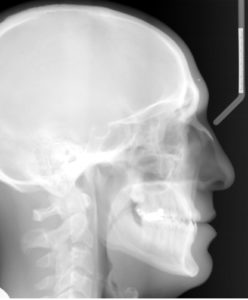

A 34.7 year old Caucasian male presents with a chief complaint that “I want to fix my bite”